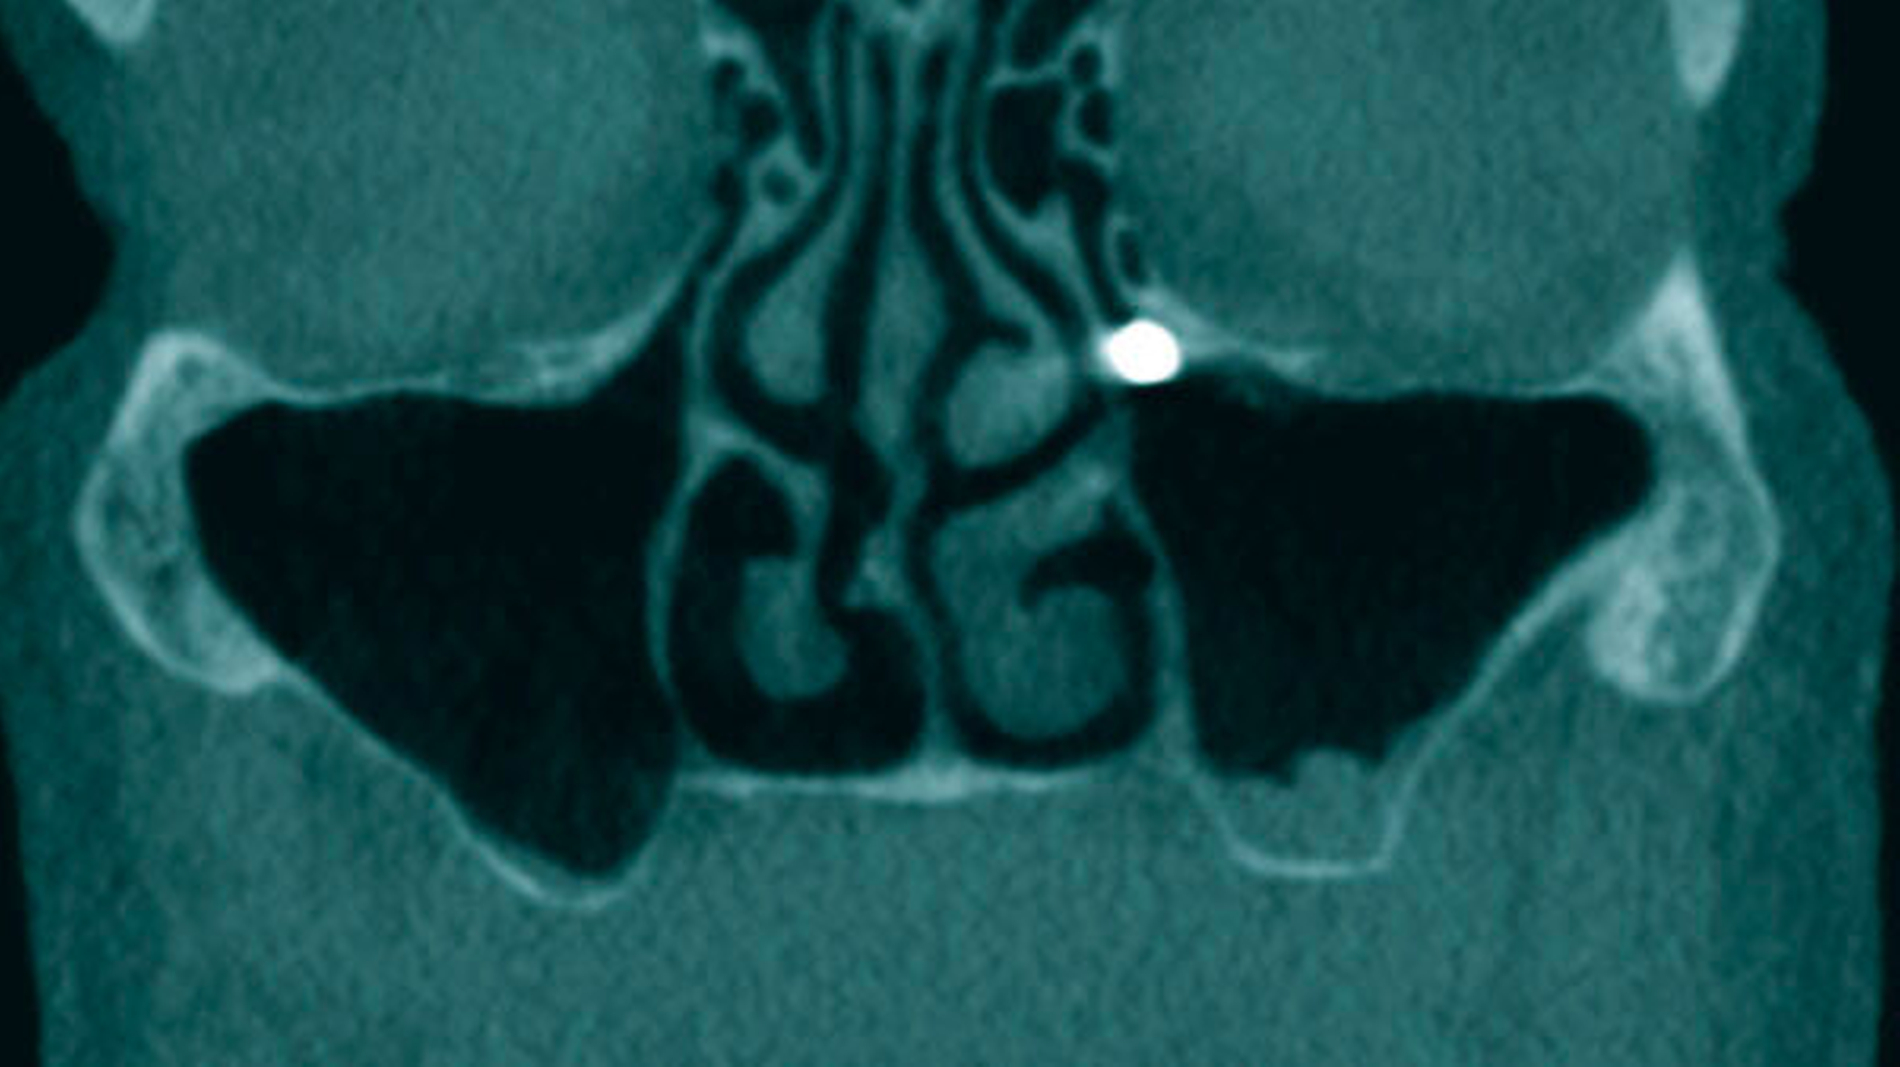

Zur weiteren Diagnostik und zur Beurteilung der Lage des Fremdkörpers wurde eine Digitalen Volumentomografie (DVT) durchgeführt. Diese bestätigte die Verdachtsdiagnose eines dislozierten Implantats im Bereich des Ostium naturale, wobei der Sinus maxillaris selbst Hinweise auf eine basale chronische Sinusitis aufwies (Abbildung 2).

Zur weiteren Diagnostik wurde auch hier eine DVT angefertigt, auf der sich in beiden Kieferhöhlen jeweils ein Implantat identifizieren ließ. Der linke Sinus maxillaris zeigte das Bild einer totalen Kieferhöhlenverschattung bei Verdacht auf Flüssigkeitsansammlung, die rechte Kieferhöhle wies keine Entzündungszeichen auf (Abbildung 6).